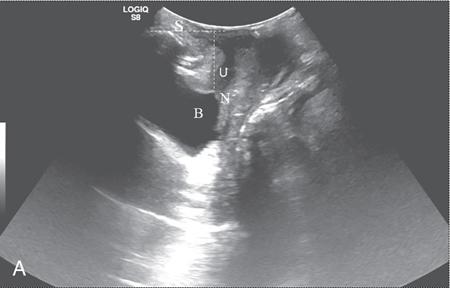

PELVIC FLOOR IMAGING – ANTERIOR AND MIDDLE COMPARTMENTS Anu Epean, Deepa Korula The term ‘Pelvic floor disorder’ refers to dysfunction of the pelvic floor musculature and connective tissues which provide support for the pelvic organs. This can produce a wide range of symptoms such a urinary incontinence, straining to void, dyspareunia, constipation, faecal incontinence and organ prolapse. The greatest risk factors for pelvic floor disorders are female sex and advanced age. Other risk factors include obesity, pregnancy, multiparity, smoking, connective tissue disorders. The pelvic floor is broadly divided into three compartments. The bladder and urethra form the anterior compartment. The vagina and uterus form the middle compartment and the posterior compartment comprises of the rectum and anal canal (Fig. 7.16.1.1). The attachment of the fascia, muscles and the ligaments to the bony pelvis form the support for these structures. From cranial to caudal, there are three layers which make up the pelvic floor – the endopelvic fascia, the pelvic diaphragm and urogenital diaphragm. This is the most cranial layer of pelvic floor, lying deep to peritoneum. It is a fine structure, comprising of a network of connective tissue which encases the pelvic viscera, provides support to the pelvic organs and maintains their anatomic relationship. There are several condensations of this fascia and ligaments which provide support in each of the pelvic compartments. In the anterior compartment, a fascial condensation called pubocervical fascia extends from anterior vaginal wall to the pubis. Tear in the pubocervical fascia can cause cystocele and urinary incontinence. There are three groups of ligaments which provide urethral support – periurethral, paraurethral and pubourethral ligaments. The periurethral ligaments arise from medial fibres of pubococcygeus and pass ventral to urethra. The paraurethral ligaments connect the lateral wall of urethra to periurethral ligament and pubourethral ligament connects the lateral wall of urethra to arcus tendineus. The urethra lies on a Hammock-like supportive layer of endopelvic fascia and anterior vaginal wall, which are stabilized by attachment laterally to arcus tendineus and levator ani (Fig. 7.16.1.2). In the middle compartment, condensations of the endopelvic fascia which attach the uterus to the lateral pelvic wall is called parametrium, which is made up of the uterosacral and cardinal ligaments. The uterosacral cardinal ligament complex supports and suspends the cervix and upper vagina above the levator plate. More inferiorly, the paracolpium attaches the vagina to the lateral pelvic wall. There are three levels of fascial support to the vagina: In the posterior compartment, the perineal body located within the rectovaginal septum supports ligaments and muscles and prevents abnormal widening of levator hiatus (Fig. 7.16.1.3). The rectovaginal fascia extends from posterior wall of vagina to anterior rectal wall. A tear in the rectovaginal fascia is the cause for an anterior rectocele. Arcus tendineus levator ani (ATLA) is formed by the condensation of the endopelvic fascia laterally, along the pelvic sidewall. This extends obliquely from inferior pubic symphysis to ischial spine and provides lateral support to the pelvic organs and attachment of the levator ani. Fascial condensations are not visualized on imaging; however, organ prolapse, due to deficiency in any of these, can be detected on MRI. The levator ani and the coccygeus muscles make up the pelvic diaphragm. The levator ani is the primary muscle of the pelvic diaphragm and is attached to the pubis and to the ATLA laterally on both sides. The slow twitch fibres of the levator ani continuously contract, maintaining tone to the pelvic floor and suspending the pelvic organs in the correct position. The two most important components of the levator ani are the iliococcygeus and puborectalis muscles. The iliococcygeus arises from external anal sphincter and has a curved shape, concave inferiorly. It fans out laterally to its insertion in the posterior part of arcus tendineus (Fig. 7.16.1.4A and B). Posteriorly, in the midline, condensations of ilococcygeus form a firm raphe anterior to coccyx called the anococcygeal ligament or levator plate. The pubococcygeus muscle is a component of the levator ani. It forms the anteromedial part and is a thick bundle of fibres arising from the pubis and anterior portion of arcus tendineus. It extends horizontally back to behind the rectum, medially forming the margin of urogenital hiatus (Fig. 7.16.1.5A). The anorectal and urogenital hiatus are closed by the contraction of the pubococcygeus muscle. This enables support during rest and in situations where the intraabdominal pressure is increased. The medial fibres of pubococcygeus, depending on their attachment to urethra, vagina, anus and rectum are termed as pubourethralis, pubovaginalis, puboanalis and puborectalis, collectively as pubovisceralis. The puborectalis forms a sling around the rectum (Fig. 7.16.1.5B). The muscles of the pelvic diaphragm are well delineated on MRI. The urogenital diaphragm or perineal membrane is the most caudal layer of the pelvic floor. It has a triangular appearance, extending from the pubic symphysis and the ischiopubic ramus to the posterior perineal body. It is ventral to the external anal sphincter and perineal body. It is attached to the surrounding structures such as the perineal body, external anal sphincter, vagina and the bulbocavernosus muscle. Imaging has an increasing role in the evaluation of pelvic floor disorders. Clinical examination alone has a low sensitivity and specificity for the detection of multicompartment involvement and organ prolapse. Imaging helps to detect involvement of multiple pelvic compartments and thus to plan surgery. Ultrasound, MRI and conventional imaging which includes voiding cystourethrography, evacuation proctography and dynamic cystocolpoproctography (DCP) are used to evaluate the pelvic floor. It is easily available, cheap and does not involve ionizing radiation. In the evaluation of the anterior compartment, ultrasound is more reliable than MRI. Transperineal ultrasound using 2D, 3D or 4D techniques along with dynamic imaging helps to evaluate pelvic floor dysfunction. Patient is placed in a dorsal lithotomy position for a transperineal scan although a standing position can also be used. Convex transducer (2–6 MHz) or endoluminal transducers (endovaginal/endorectal) maybe used. In a midsagittal translabial scan, the anatomic relationship of urethra, bladder, vagina, cervix and anorectum can be studied and the relative position of these organs determined by use of certain measurements. The bladder-symphysis distance (BND) is the distance between the bladder neck and lowest margin of symphysis pubis and demarcates position of the bladder neck. Measurement of BND is made at rest and during Valsalva manoeuvre and the difference in BND between the two, gives the measure of bladder neck descent. There are no definite values to indicate normal descent but there is a proposed cut off of 20, 25, 30 mm to indicate hypermobility (Fig. 7.16.1.6A and B). The proximal urethra rotates posteroinferiorly during Valsalva manoeuvre and this can be measured by the posterior urethrovesical angle (β) or the gamma angle. The posterior urethrovesical or retrovesical angle (β) is the angle between a line through the urethral axis and the line through the trigonal surface of the bladder and varies from 90–120 degrees normally. This may increase to 160–180 degrees and can be associated with funnelling of bladder neck. The gamma angle is the angle between a line through the inferior margin of pubic symphysis and the urethrovesical junction. This is seen on Valsalva manoeuvre or at rest in patients with stress incontinence (Fig. 7.16.1.7). Color Doppler can demonstrate urine leakage on performance of Valsalva or at rest. Other abnormalities that can be detected on transperineal ultrasound are cystocele, urethral diverticulum, Gartner duct cyst, foreign body or bladder tumour. 3D pelvic ultrasound is useful to evaluate pelvic floor dysfunction and to study the urethra, levator ani complex, paravaginal supports, prolapse and implant imaging. 4D ultrasound helps in real-time, dynamic imaging of pelvic floor. In the middle compartment, although uterine prolapse is often clinically evident, it can also be detected by ultrasound. Uterine prolapse can be also quantified by measuring maximum descent of uterus from the reference point which is the inferior margin of pubic symphysis. Ultrasound is also useful to evaluate for surgical planning in a large retroverted uterus with an anteriorly placed cervix causing voiding symptoms. MRI is useful in the evaluation of pelvic floor as it provides good anatomic detail about the pelvic floor muscles, ligaments because of its inherent superior soft tissue resolution. In addition, dynamic MRI yields functional information. MRI defecography is a dynamic study performed to study the posterior pelvic compartment but it also gives information about the anterior and middle compartments. It can be performed both with closed magnet and open magnet systems. The patient is positioned supine with phased array coil around pelvis in a closed magnet system. In an open magnet system, the patient is in a sitting and more physiological position; however, due to the lower signal to noise ratio and lower resolution, a closed magnet system is preferred. Bowel preparation with use of laxative on night before the scan is optional. Voiding prior to the study is encouraged since an overdistended bladder can cause misinterpretation of results. Presence of some urine in the bladder is however, helpful to detect anterior vaginal prolapse. Instructions are given to the patient, prior to the procedure, about the ‘rest’, ‘squeeze’, ‘strain’ and ‘defecate’ phases of dynamic imaging, to ensure that movement or lifting of the pelvis does not occur during these manoeuvres. The rectum is filled with up to 200 mL of ultrasound gel. The patient is made to wear an adult diaper and covered with an incontinence pad on the gantry. Vaginal gel, ∼50 mL maybe introduced since this helps to delineate anatomic landmarks and detect uterovaginal prolapse. Initial large FOV T1 localizer scans help to identify the midline sagittal section of pelvis. T2-weighted fast spin echo, high-resolution sequences in sagittal, axial, coronal planes are used to obtain anatomic detail. This is followed by dynamic imaging of the pelvic floor with use of steady state imaging sequences such as True fast imaging with steady state precession (TrueFISP Siemens) and balanced fast field echo (balanced FFE Philips). Steady state sequences have the advantage of short acquisition times and higher signal to noise ratio and hence useful to obtain rapid serial midsagittal images while patient performs ‘squeeze’, ‘strain’ and ‘defecates’. There are several points and lines for measuring and staging pelvic organ prolapse on MRI; however, the PCL line is said to have the highest interobserver and intraobserver reliability of MRI measurements compared to all proposed reference lines and is described below: Pubococcygeal line (PCL): defined as the line that connects the inferior portion of the pubic symphysis to the last coccygeal joint. The PCL is the most commonly used reference line for the assessment of pelvic floor disorders (Fig. 7.16.1.8).